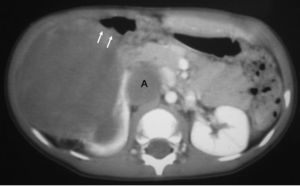

El sarcoma de células claras tuvo lugar en un niño de 2 años estudiado por masa abdominal, en el que se identificó una masa intrarrenal, de predominio necrótico y una adenopatía retrocava (fig. 8).

Fig. 8. Sarcoma de células claras. Tomografía computarizada abdominal con contraste intravenoso. Corte sobre polo inferior renal. Masa en riñón derecho, sólida, hipodensa, con gran crecimiento extrarrenal y que desplaza colon ascendente hacia delante (flechas). Adenopatía retrocava, hipodensa (A) de 3 cm.